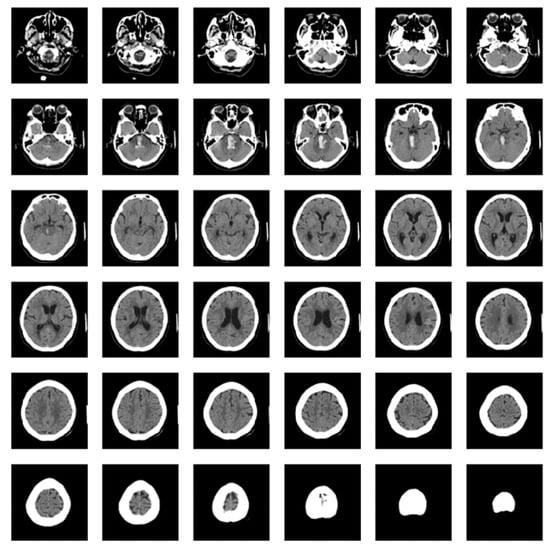

As shown in Figure 1, each brain CT scan consisted of 30–50 individual images combined to create 3D images. These 3D images were then used to train models to classify a patient depending on the presence or absence of an ICH.

Figure 1. Images of one brain computed tomography dataset.